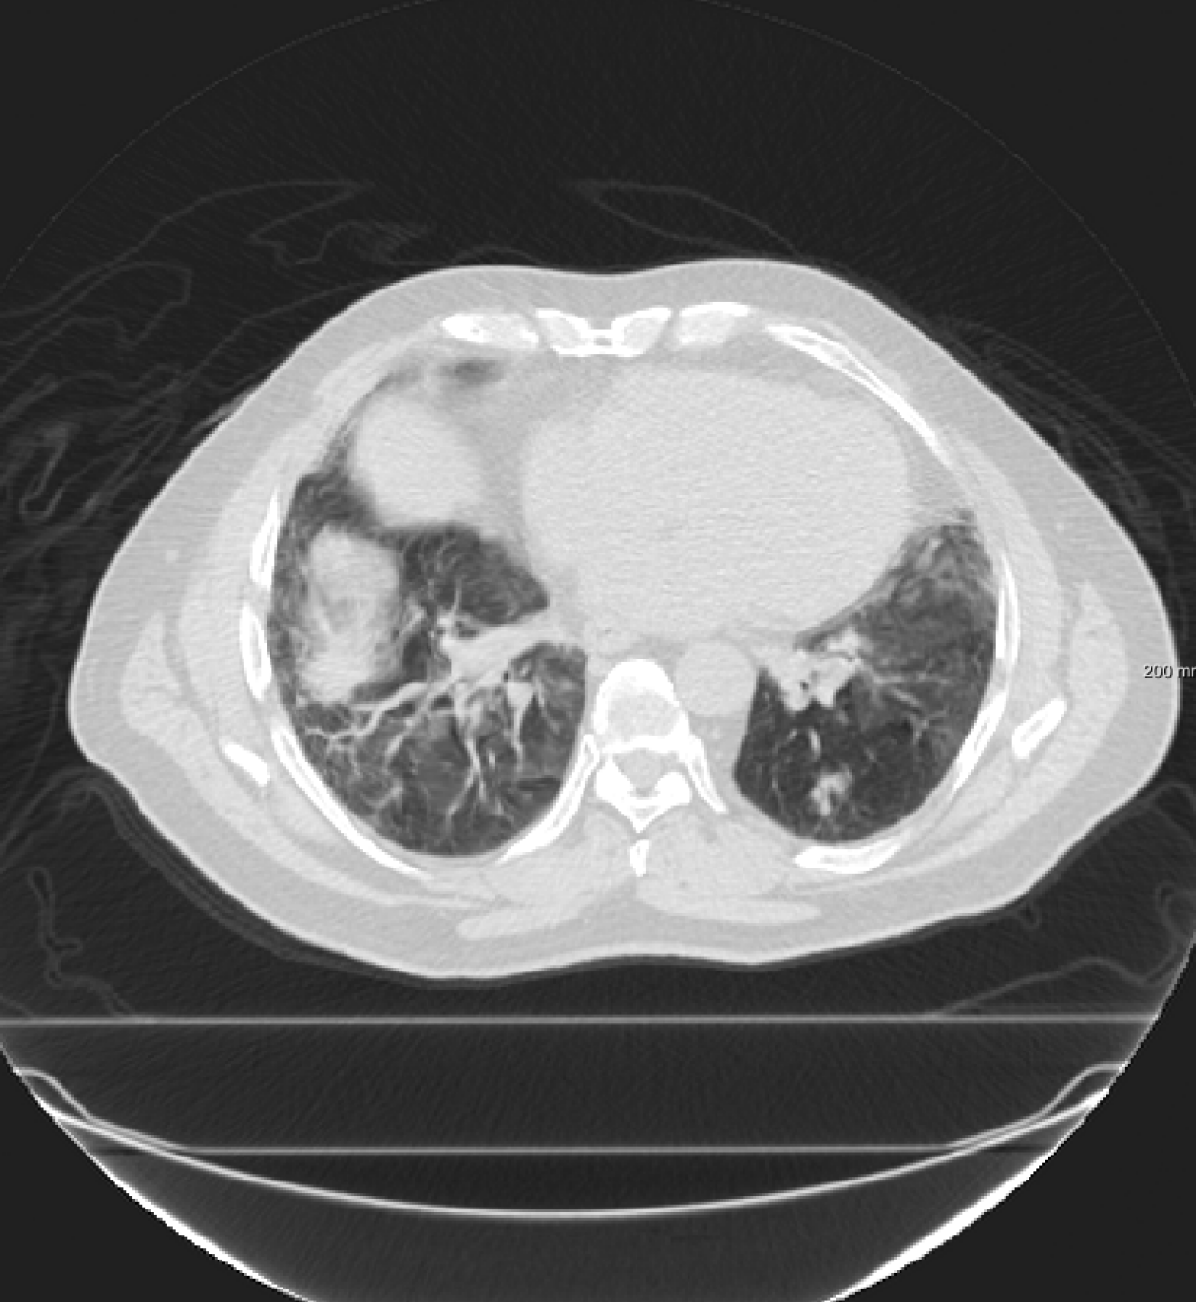

Three chest CT scan datasets are used in this study: The SPREAD (Stolk et al., 2007), the DIR-Lab-4DCT (Castillo et al., 2009) and the DIR-Lab-COPDgene dataset (Castillo et al., 2013).

In the DIR-Lab-COPDgene database, ten cases with severe breathing disorders are available in inhale and exhale phases. The average image size and the average voxel size are and mm, respectively. In each pair, 300 landmarks are annotated.

For the DIR-Lab-4DCT database, a comparison between RegNet and affine, B-spline (three resolutions), an advanced conventional registration method using sliding motion (Berendsen et al., 2014) and three other CNN-based methods (Eppenhof and Pluim, 2018; de Vos et al., 2019; Sentker et al., 2018) is available in Table IV. It can be seen that training with “S+M” improved performance slightly with respect to just “S”. Adding the respiratory motion category improved performance substantially, as these are inhale-exhale pairs; this is predominantly caused by the patients where the TRE after affine registration was still quite large. An example visualization is also available in Fig. 5(f), showing that adding the respiratory motion category can align images better in the diaphragm region. The advanced conventional registration method that leverages sliding motion (Berendsen et al., 2014) is still better than RegNet. Note that RegNet was not trained on the DIR-Lab-4DCT data, similar to Eppenhof and Pluim (2018); Sentker et al. (2018). However, de Vos et al. (2019) and Eppenhof and Pluim (2018)-DIR methods were trained on the same database but using cross-validation to report the results. Also note that the results reported in Sentker et al. (2018) are averaged over all phases of DIR-Lab-4DCT (T00 to T10), while the results of other CNN methods (including RegNet) are reported between the maximum inhale and maximum exhale phase (T00 and T50). These reported results are therefore likely somewhat better than the results for T00 and T50 only.